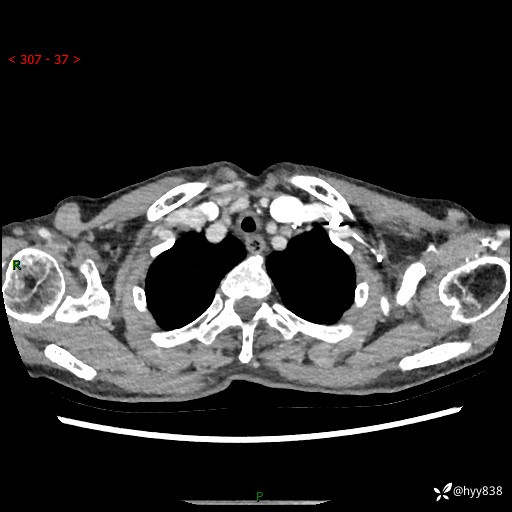

胸部CT平扫+增强